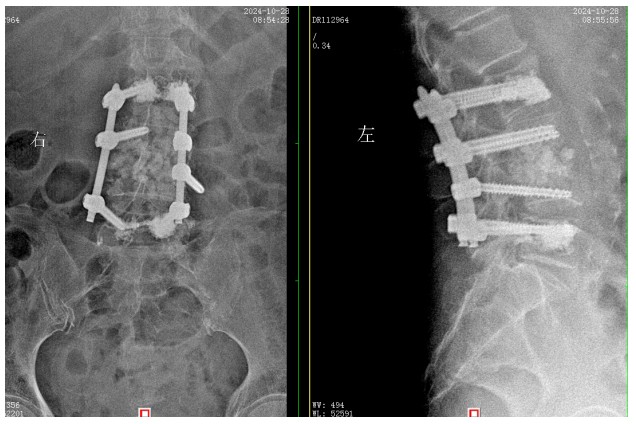

經(jīng)過積極充分的準(zhǔn)備,錢軍博士團隊為患者成功實施了L3、L4脊柱結(jié)核病灶清除植骨融合內(nèi)固定術(shù),手術(shù)順利,術(shù)后患者腰腿痛癥狀明顯緩解,患者及家屬對治療效果非常滿意,對醫(yī)院的醫(yī)療技術(shù)以及優(yōu)質(zhì)的服務(wù)護理稱贊不已。